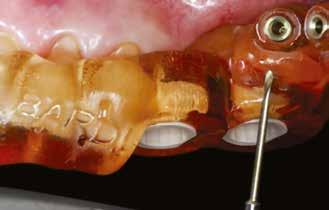

A rendelőnkben szokásos protokoll szerint digitális lenyomatot vettünk az alsó és felső állcsontokról a DEXIS IS 3800 intraorális szkennerrel (4. a–c ábra). A kiindulási állapot rögzítésére szájfotókat is készítettünk. Az ideiglenes kivehető fogpótlás ezekre a digitális mintákra készült.

Annak érdekében, hogy a fogeltávolítás és a végleges pótlás átadása közti időben biztosítani tudjuk a páciens számára az esztétikus megjelenést és a funkcionalitást, ideiglenes, kivehető fogpótlást készítettünk (6. ábra) Mivel a pácienst beküldő fogorvos szintén évek óta digitális eszközökkel dolgozott, az ideiglenes pótlások digitális lenyomatokra és 3D nyomtatott mintákra készültek.

A tízhetes gyógyulási idő leteltével ellenőriztük az implantátumok stabilitási hányadosát (ISQ). A következő lépés a végleges fogpótlás elkészítése, amelyet a páciens beküldő fogorvosa fog végezni. A csavarral rögzülő monolitikus hídpótláshoz a lenyomat intraorális szkennerrel készül, valamint a fogtechnikai lépéseknél is törekedni fognak a lehető legnagyobb mértékű digitalizálásra.